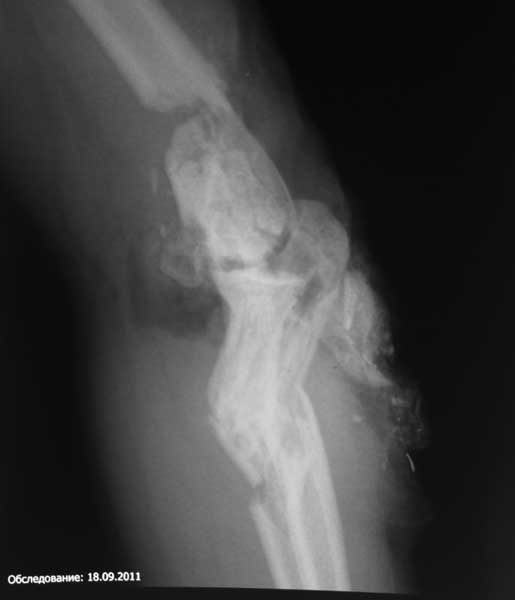

2. КТ локтевого сустава с 3D реконструкцией. Надо определиться и понять, что осталось от дистального метаэпифиза плечевой кости, - от этого будет зависеть и дальнейшая тактика. Здесь теорию прекращаем и ждем результатов КТ.

Насколько оправдано снятие аппарата? В АВФ удобнее мыть, перевязывать, не так ли? Штанги графитовые и больших наводок при рКТГ не дадут. Выкладываю свежие рентгенограммы.

Согласен, при таком "качестве" снимков КТ необходимо. По поводу дистального метафиза - при благоприятном сопоставлении суставных опорных поверхностей - дефект заполнить не составит большого труда.